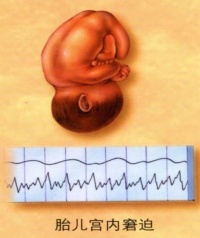

胎儿窘迫

胎儿在宫内有缺氧征象危及胎儿健康和生命者,称为胎儿窘迫(fetal distress)。胎儿窘迫是一种综合症状,是当前剖宫产的主要适应征之一。胎儿窘迫主要发生在临产过程,也可发生在妊娠后期。发生在临产过程者,可以是发生在妊娠后期的延续和加重。

胎心出现异常改变是胎儿窘迫最早出现的症状,胎儿的正常心率为120~

160次/分,160次以上或120次以下均属不正常,低于100次表示严重缺氧。窘迫时先是表现为胎心加快,而且心跳规则、有力,之后心跳开始变慢、变弱,节率也变的不规则。但应注意,当子宫收缩时,由于子宫-胎盘的血液循环暂时受到干扰会使胎心变慢,而当子宫收缩停止后,胎心很快就恢复正常,因此应以两次子宫收缩之间的胎心为准。